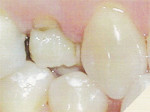

ancienne obturation - Ancienne obturation

Une dent déjà obturée sur deux ou trois faces présente une nouvelle carie sous ou à côté de cette obturation. Mais la matière profonde subsiste.